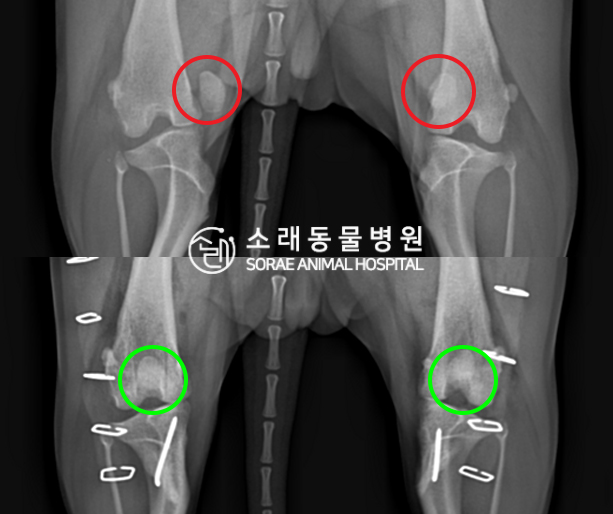

수술전과 수술후에 촬영한 심뽄희의 슬개골

방사선 사진입니다. 나란히 놓고 비교해보니

슬개골의 위치에 확연한 차이가 있는 것을

확인해 볼 수 있는데요. 내측으로 탈구되어 있던

슬개골이 원래 제자리인 활차구에 예쁘게

자리 잡고 있는 모습을 확인할 수 있었습니다.